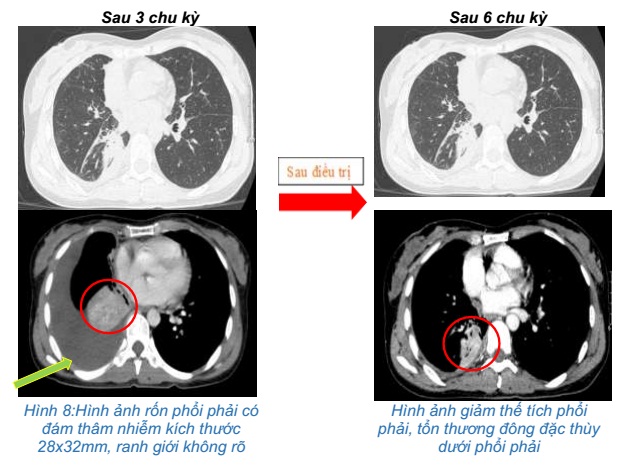

- Chụp cắt lớp vi tính ngực:Khối vùng rốn phổi phải gây xẹp phổi kích thước 28x32mm. Dịch khoang màng phổi phải dày 50mm. Khống thấy hạch to trung thất

Đánh giá sau 6 chu kỳ điều trị:

- Chụp cắt lớp vi tính ngực:Giảm thể tích phổi phải, tổn thương đông đặc thùy dưới phổi phải, dịch màng phổi phải dày 6mm.

- Chụp cắt lớp vi tính bụng: Nốt giảm tỷ trọng nhu mô gan phải, kích thước 12x14mm, ngấm thuốc kém sau tiêm

Sau 6 chu kỳ điều trị:

Sau điều trị hoá trị kết hợp Pembrolizumab cho thấy: U phổi giảm kích thước, hạch trung thất không còn, chất chỉ điểm khối u CEA, Cyfra 21-1 giảm về giới hạn bình thường, tổn thương di căn gan các nốt nhu mô gan giảm bớt. Bệnh nhân không gặp tác dụng phụ đáng kể nào trong quá trình điều trị.